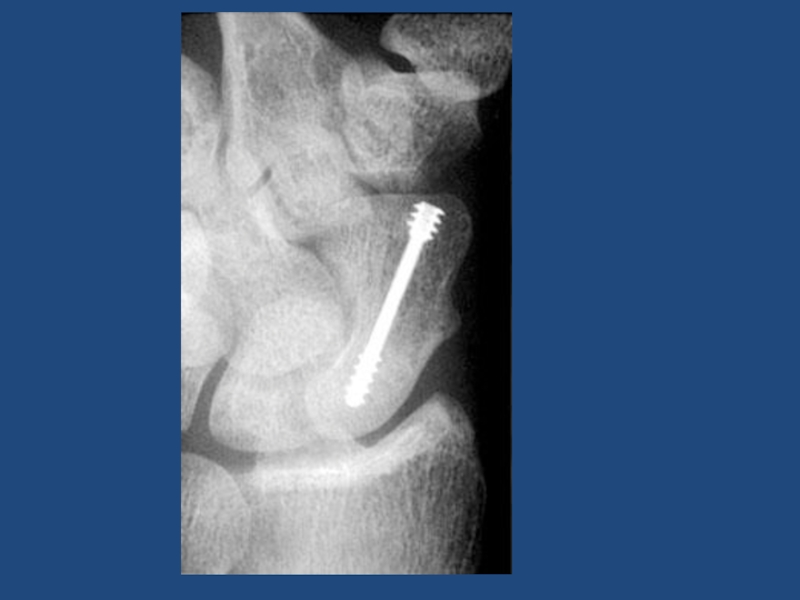

Слайд 66Срастающийся поперечный перелом нижней трети бедра. Накостный остеосинтез шурупами

Срастающийся поперечный перелом нижней трети бедра. Накостный остеосинтез шурупами